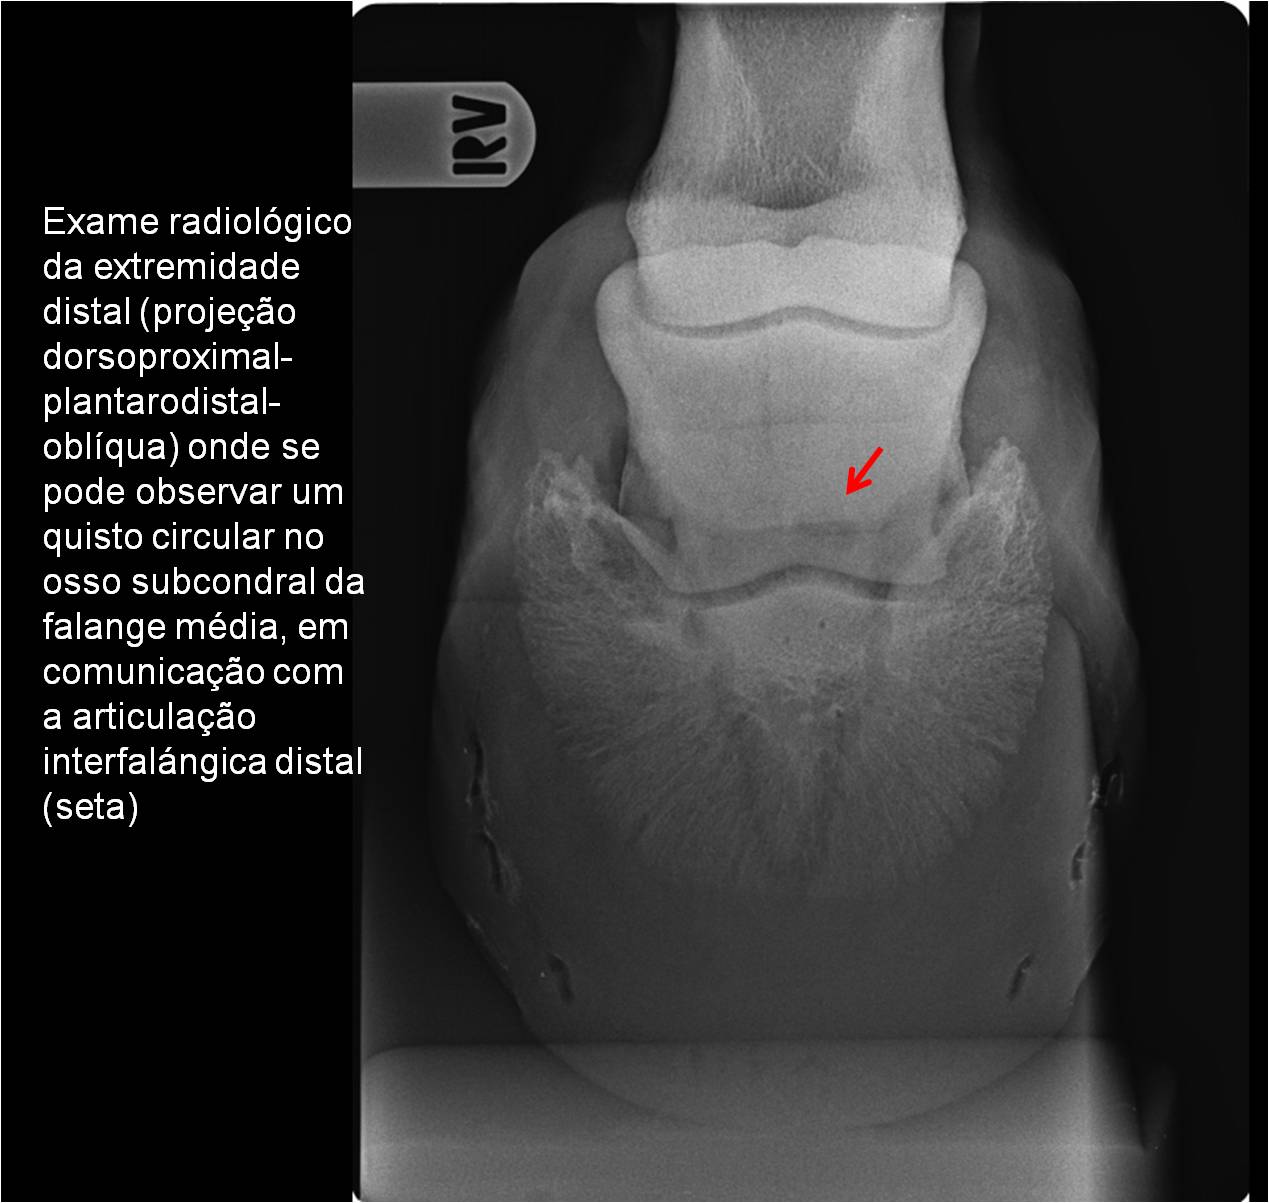

Publisher: Universidade de Évora

Abstract: O relatório de estágio encontra-se estruturado em três partes distintas. A primeira parte faz a caracterização das infraestruturas e funcionamento do Hospital Veterinário de Equinos de Lüsche, Oldenburg, Alemanha, assim como a análise casuística dos casos clínicos acompanhados durante os 6 meses de estágio. A segunda parte consiste de uma revisão bibliográfica sobre quistos do osso subcondral em equinos. Por fim, a terceira parte consta da apresentação e discussão de um caso clínico, nomeadamente o diagnóstico e acompanhamento imagiológico, por ressonância magnética, de um quisto subcondral na terceira falange num cavalo adulto; ### Abstract Equine Practice- Subcondral bone cyst of the third phalanx This internship report is divided in three parts. The first part characterizes the infrastructure and function of the Equine Hospital Lüsche, Oldenburg, Germany, as well as the casuistic of the clinical cases accompanied during the 6 month internship. The second part consists in a bibliographic review of cystic lesions of the subchondral bone in equines. The third part consists in a case report, the diagnostic and imagiological accompaniment, by use of magnetic resonance imaging, of a subchondral bone cyst in the distal phalanx of an adult equine.